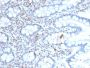

Positive Control

293T, NIH3T3, HeLa or Jurkat cells. Colon Carcinoma.

Antibody applications

IHC, FFPE (verified)|WB (verified)

IHC (FFPE) (verified)|WB (verified)